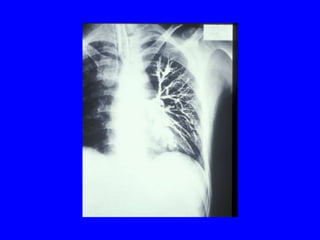

POST-OBSTRUCTIVE

BRONCHIECTASIS

• Focal or localized because only distal to the

obstructing lesion

• Dilated bronchi distal to obstruction filled

with mucus instead of air